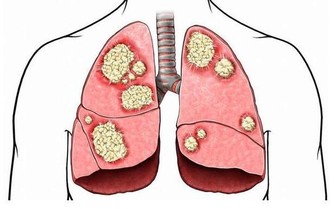

據統計,全球每年有22萬以上女性患上卵巢癌,其中約有六成患者死亡。卵巢作為女性的內生殖器官,因為位置比較深,初起癥狀輕微,所以很難被察覺,待到發現時,已經到了晚期,這時已經失去最佳治療時間。

卵巢在腹腔內部,常規的婦科檢查一般只能查到卵巢囊腫,進而以為它只是一種普通的婦科疾病。而且,女性生理周期紊亂也會引起卵巢囊腫,但這種囊腫在生理期后就會恢復正常。但有病變的囊腫則不然,它們經期后並不會恢復,這時需要進一步檢查,才能判斷它到底是正常的卵巢囊腫還是卵巢腫瘤。

由於檢測技術有限,目前還不能從外部確定卵巢疾病。即使用B超、彩超也只能查出個大概,再加上內分泌功能、胚胎髮育等因素的影響,使卵巢癌在早期並無明顯癥狀。